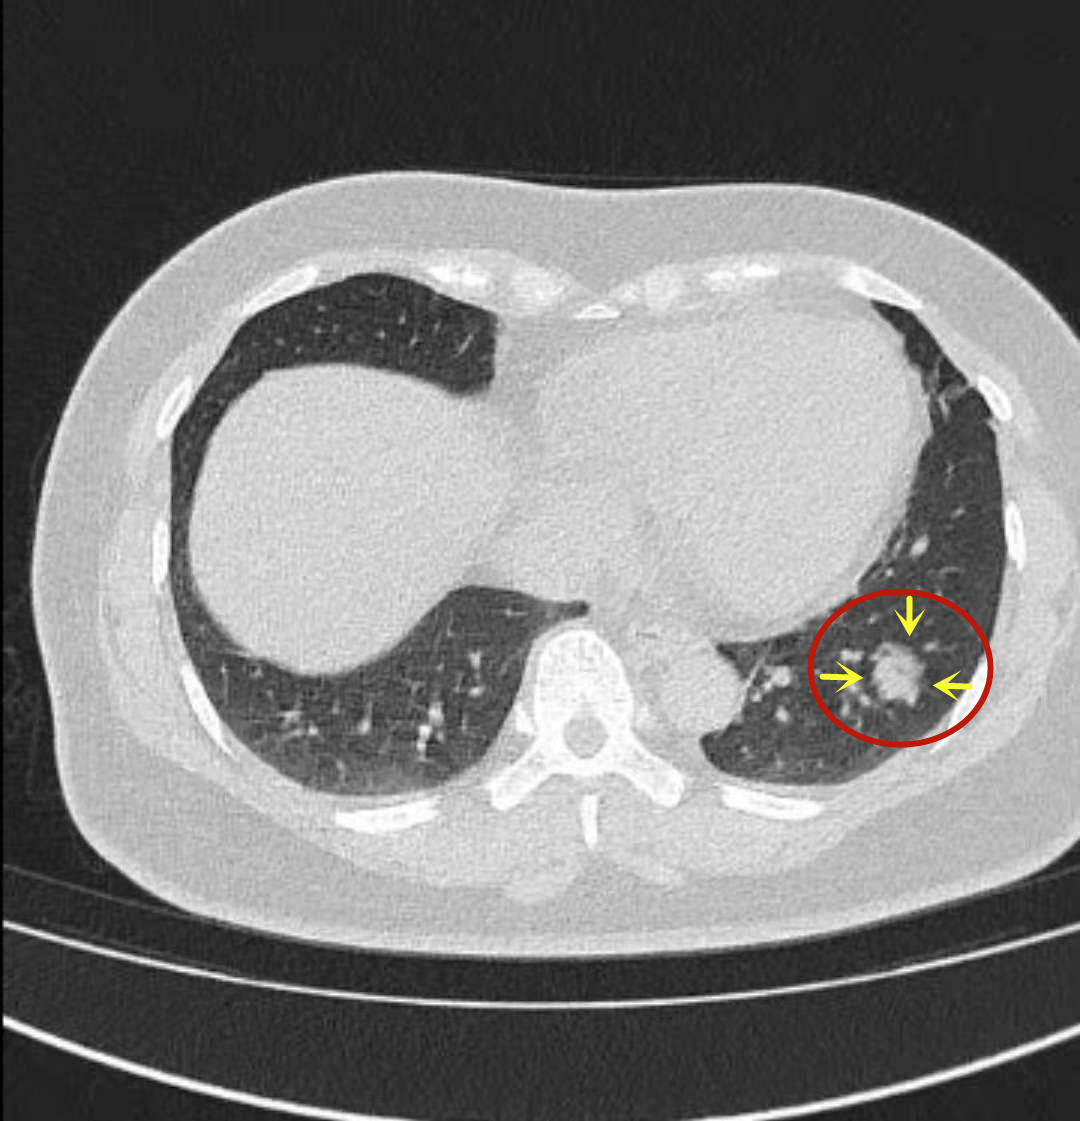

图2-7是入院前1月余时CT见左下叶基底段的结节。其病灶基本实性,但不显得致密;边缘光滑,不似平常的浸润性腺癌表现,没有毛刺征或收缩牵拉胸膜。虽然肺癌不能除外,但疑点较多:病灶密度不够致密、边缘过于光滑、缺乏收缩力、有些边缘太过平直缺乏膨胀性。建议试口服莫西沙星9~12天,之后过1个月左右再来复查左下叶靶扫描。